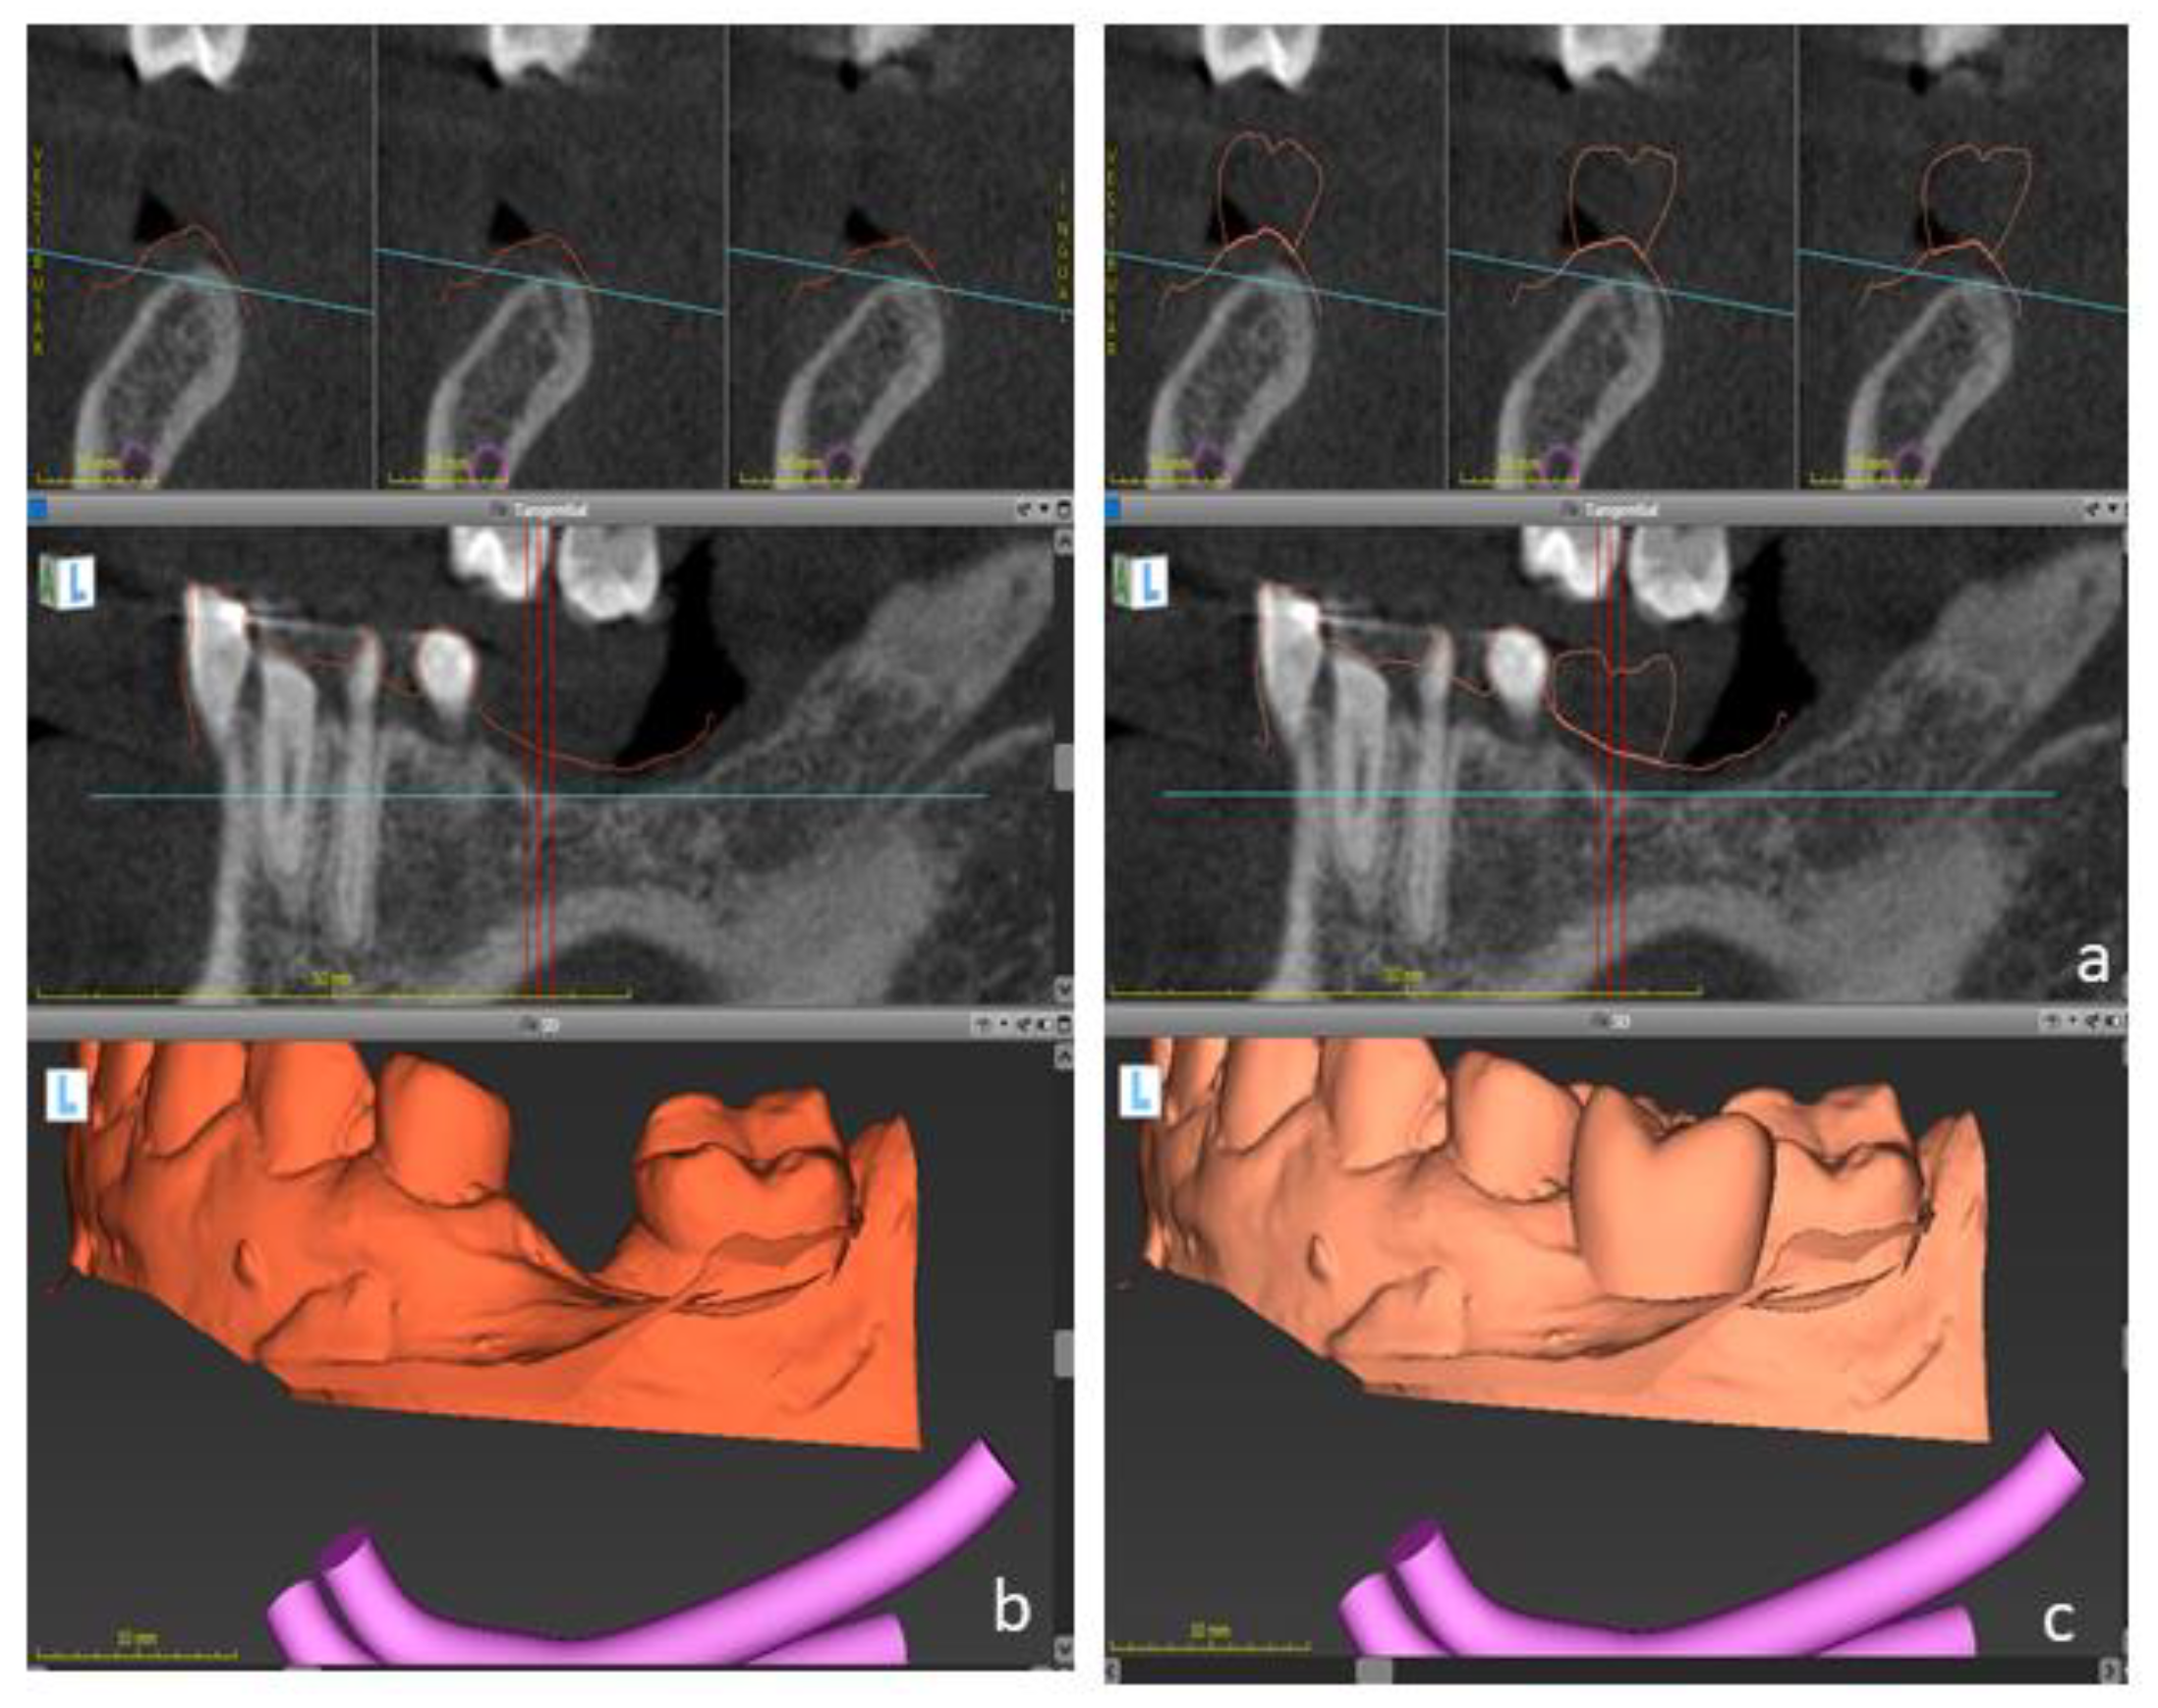

2.1. Case One

2.2. Case 2